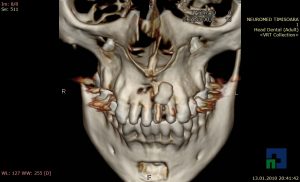

- Diagnosticul fracturilor:

- Unice

- Multiple

- Cu înfundare

- Complexe cranio-sinusale

- Complexe cranio-etmoidale

- Complexe cranio-orbitare

- Complexe cranio-faciale